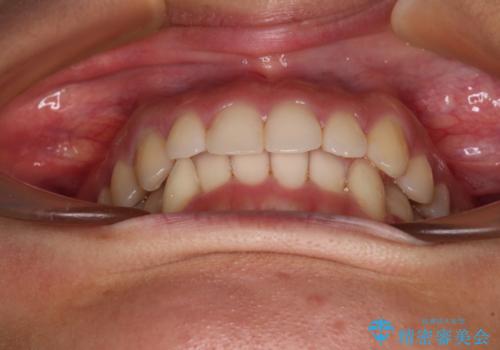

- 下顎の八重歯を気にして来院された患者様です。

下顎前歯にデコボコが集中していたため、顎間ゴムによる後方移動とIPR(歯と歯の間を削ること)により歯列を整えることとしました。

しっかりとマウスピースを装着してくださったおかげで、スムーズに治療を終えることができました。